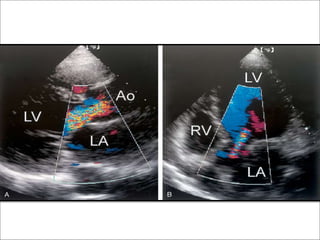

Height of AR jet

• From parasternal long axis view – the height of the jet just below

the valve can be measured using electronic calipers.

• Dimension expressed as the percentage of LVOT dimension to

provide an estimate of severity.

Jet height/outflow tract dimension ratio.

• Greater the percentage – the more severe the regurgitation.

• A jet that occupies more than 60% of the LVOT(either height or

area)usually indicates severe AR.

• Short axis view at the level of great arteries – area of jet compared

to aortic orifice.

Jet Height/LVOT height (PL ax)

1+ 1-24%

2+ 25-46%

3+ 47-64%

4+ >65%

Jet area

• In PSax view

• Using color doppler

• Compared to LVOT area

1+ 0-3%

2+ 4-24%

3+ 25-59%

4+ >60%